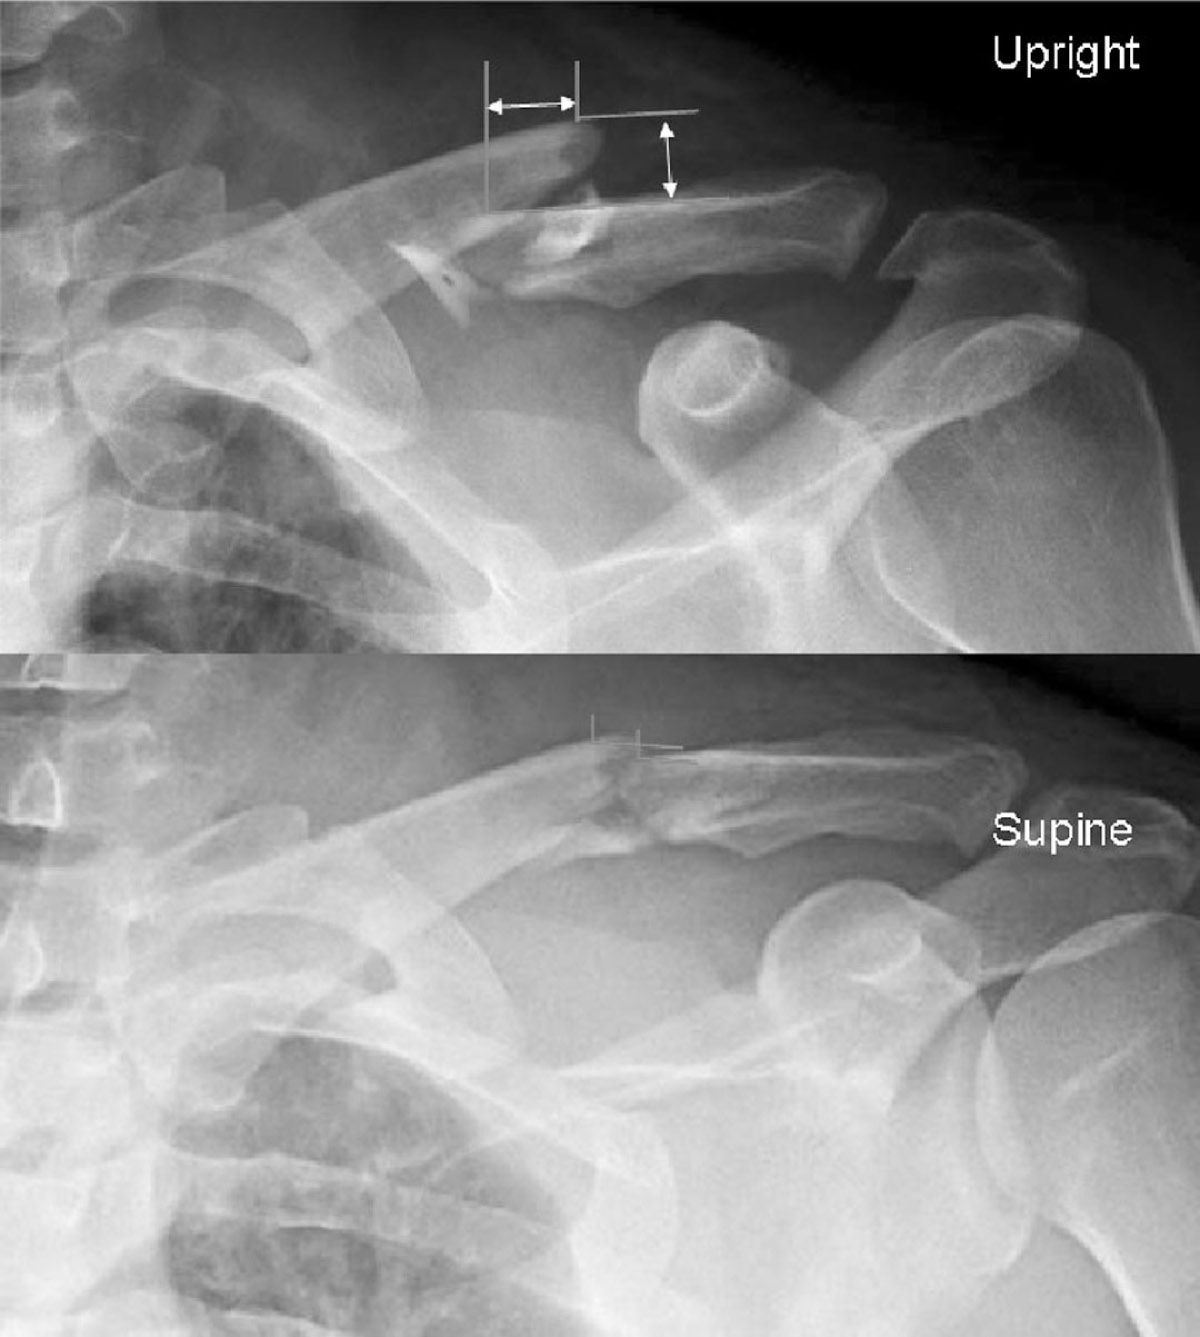

From radiopaedia.org

Clavicle fracture Image Common Clavicle Fracture Location  Here we will look at the common causes and symptoms of clavicle fractures, how they are diagnosed and treated, how to make the best recovery and common problem associated with a broken collarbone. A clavicle fracture is a break in the collarbone, one of the bones in the shoulder. Fracture in the middle portion (shaft) of the clavicle. Midshaft clavicle. Common Clavicle Fracture Location.